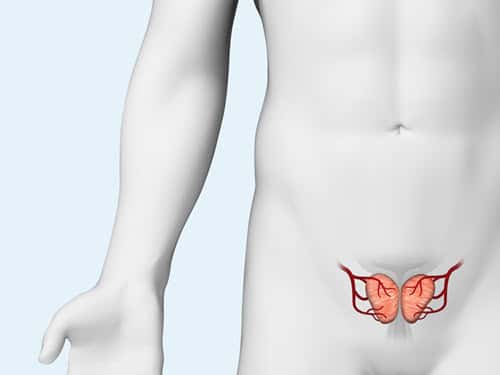

BENIGN PROSTATIC HYPERPLASIA (BPH)

Benign prostatic hyperplasia, or BPH, is the enlargement of the prostate gland and affects only men. It becomes more common as men get older. Up to 90% of men over the age of 80 have BPH. Although BPH is noncancerous, it can cause bothersome lower urinary tract symptoms.

Explore the products we offer to support prostatic artery embolization (PAE), a minimally invasive option to treat BPH.

MERIT PRODUCTS